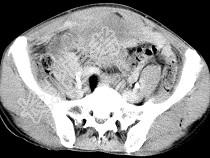

- 单项选择题男,56岁, 无规律上腹痛,左锁骨上淋巴结肿大, 消瘦、乏力,影像检查如图, 最可能诊断为 ( )

A、胃及腹腔淋巴瘤

B、胃癌并盆腔种植

C、胃溃疡穿孔

D、肠系膜淋巴管瘤

E、腹膜结核